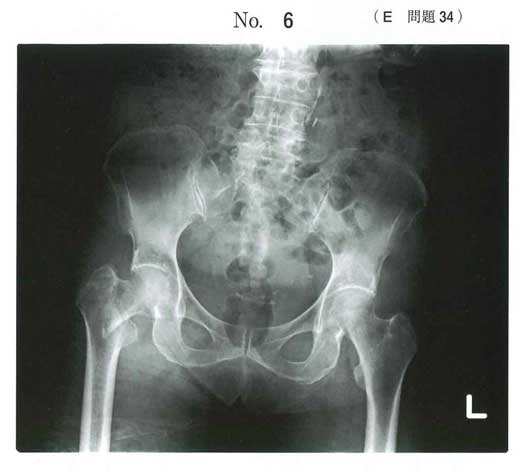

e 大腿骨近位の骨折(転子部、頸部)

高齢者の転倒で骨折が最も起こりやすい(102H19)

e 大腿骨近位部骨折

111H22と画像まったくいっしょです